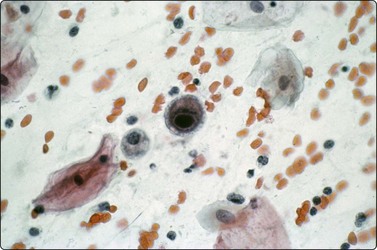

In fungal and cat scratch disease,40 suppurative granulomas with neutrophils interspersed among the epithelioid histiocytes in the granulomas may be present (Fig. 18.2).

image

Fig. 18.2 Suppurative granuloma

Neutrophils infiltrate epithelioid granuloma consisting of epithelioid histiocytes in background of neutrophils (Giemsa, ×600).